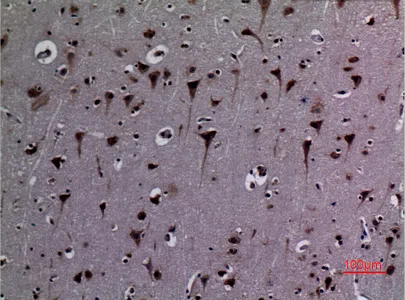

KiSS-1R Rabbit Polyclonal Antibody

Cat: APRab13039

Size1:50μl Price1:$118

Size2:100μl Price2:$220

Size3:500μl Price3:$980

Size2:100μl Price2:$220

Size3:500μl Price3:$980